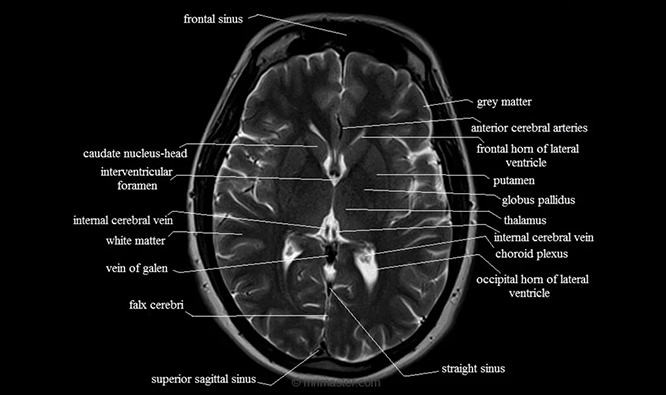

Standard Brain MRI This basic scan provides detailed images of brain structure and can detect tumors, strokes, and other abnormalities.